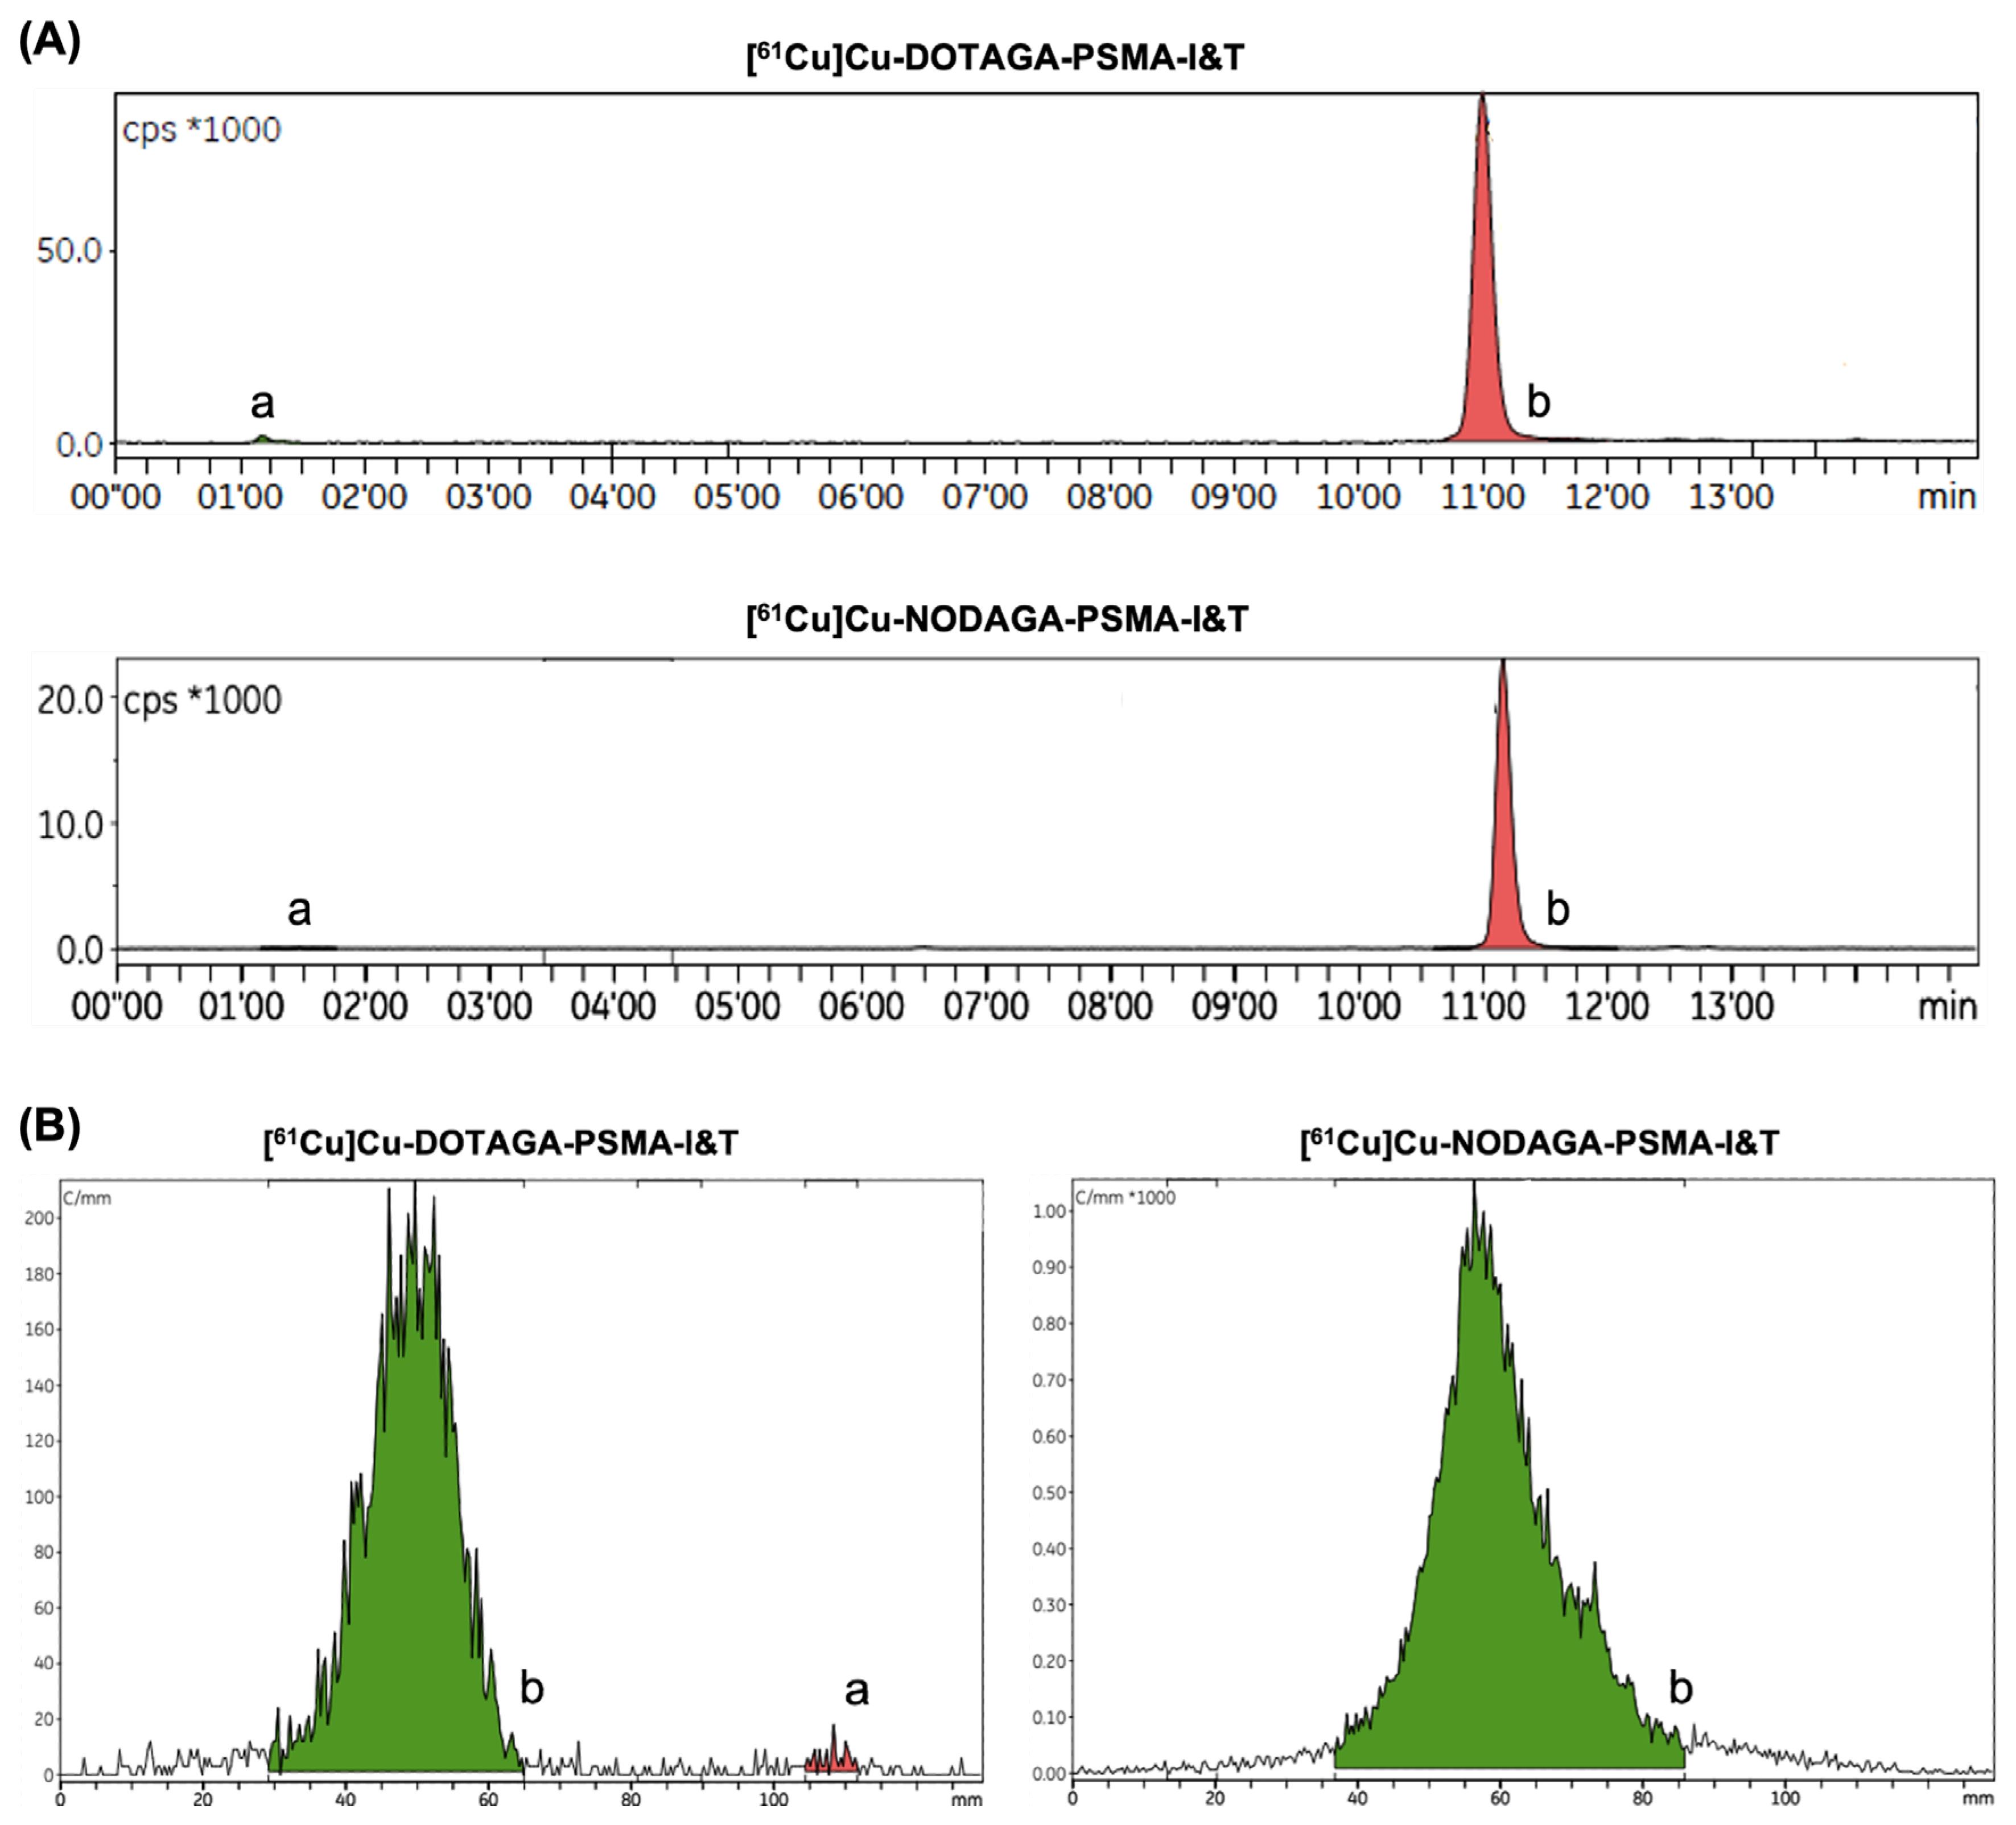

2.1. Automated Radiopharmaceutical Synthesis and Radiochemical Purity

4.3. Radiochemical Purity